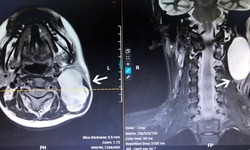

khối u vùng cổ

Y tế - 07/09/2023 17:28SKĐS - 18 tuổi, thiếu nữ ở Hà Nội có thâm niên 'đeo' khối u ở vùng cổ đã 7 năm. Khối u khiến cô luôn để tóc dài để che đi và tránh ánh mắt tò mò của mọi người; khối u khiến cổ cô bị sưng phồng, khó cử động, đôi khi xuất hiện cơn đau vùng gáy như điện giật.